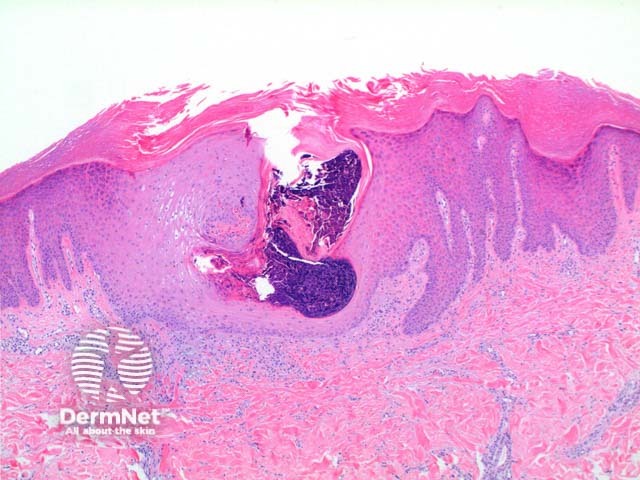

The low power view of perforating collagenosis shows an invaginating epidermal process (Figure 1). There is hyperkeratosis overlying a cup shaped depression or invagination in the epidermis. There is prominent epidermal hyperplasia, which encompasses a central basophilic plug of keratin, collagen and inflammatory debris (Figure 2). On careful sectioning, this is continuous with altered collagen in the underlying dermis, which is being expelled by the process of transepidermal elimination. Within the epidermal plug bright eosinophilic altered collagen fibres can be seen (Figures 3 and 4).

Figure 1